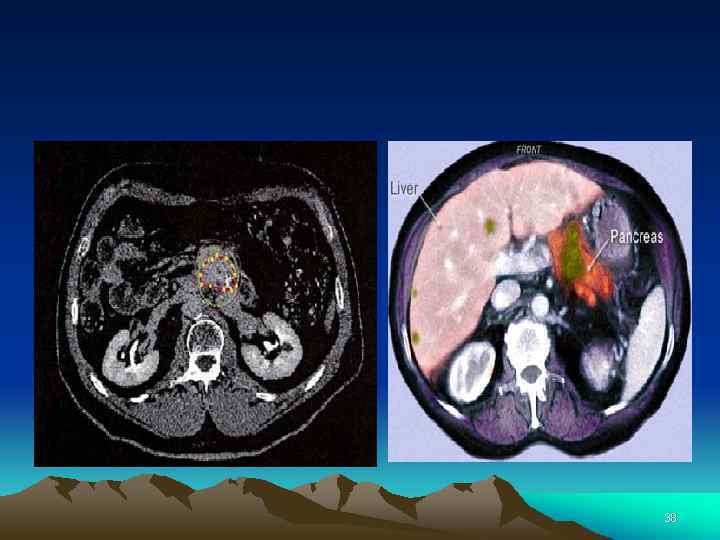

КТ-диагностика рака поджелудочной железы: современное состояние проблемы Проблема диагностики и лечения рака поджелудоч ной железы (ПЖ) остается актуальной для современной клинической онкологии. Заболеваемость раком ПЖ не уклонно растет как в нашей стране, так и за рубежом. Не смотря на совершенствование методов диагностики, хи рургической техники, появление новых противоопухоле вых препаратов, разработку комбинированных и ком плексных методов лечения больных раком ПЖ, общая 5 летняя выживаемость не превышает 5— 20% 37

38

Клинические применения: поджелудочная железа МСКТ с криволинейными мультипланарными реконструкциями при опухолях поджелудочной железы (Lawrence Chow, Stanford, USA) Протокол при раке поджелудочной железы: v Нативная фаза – срез 10 мм после дачи 900 мл воды v Поздняя артериальная – задержка 40 сек, 1, 25 мм v Портовенозная – задержка 80 сек В 11% случаев изоденсивный рак - вспомогательные признаки: v Деформация контура v Прерывание панкреатического протока v Дистальная атрофия Лишь 10 -15% пациентов имеют резектабельнй рак поджелудочной железы. Из них 30 -50% - positive margine 45

Одно из наиболее ценных преимуществ МДКТ — возможность мультипланарной реконструкции (МПР) изображений и создания трехмерных изображе ний. МПР позволяет достичь хорошего качества изобра жения с высоким разрешением, изучить зоны интереса во фронтальной, сагиттальной и других плоскостях на осно ве заданной кривой, делая изображение более наглядным и привычным для клиницистов. МПР, выполненные в различных плоскостях, помогают детализировать топо графоанатомические соотношения. 46

Трехмерное моделирование на основе МДКТ с болюсным контрастным усилением делает возможным создание объемных изображений анатомических зон, в которых показаны соотношения патологического очага, сосудов и окружающих органов. Именно эти реконструкции позволяют хирургамнаглядно оценить получаемые при КТ изображения, увидеть нужные объекты в таких ракурсах, которые в реальных условиях, на операционном столе, недостижимы (например, сзади, ≪изнутри≫ и т. д. ). Изображения, полученные после обработки данных, значительно расширяют диагностические возможности КТ, улучшают визуализацию панкреатических сосудов и протоков ПЖ. 47

Наиболее часто используемые методы постпроцессорной обработки данных: проекция макси мальной интенсивности, объемные построения, проек ции минимальной интенсивности и криволинейные пло скости. В литературе встречается множество данных о том, что МПР изображений значительно повысила диа гностические способности МДКТ в выявлении опухолей ПЖ, особенно малых размеров. Использование МДКТ ангиографии с трехмерной реконструкцией изображений дает возможность выявить пути парапанкреатической, периневральной и лимфати ческой инвазии аденокарциномы ПЖ. 48

При раке панкреатобилиарной области парапанкреатические лим фатические сосуды поражаются довольно часто, что имеет прогностическое значение. Однако в литературе очень мало данных посвящено КТ визуализации нормальной и патологически измененной парапанкреатической лимфа тической системы. При поражении раком головки ПЖ инфильтрация наиболее часто обнаруживается вдоль об щей печеночной артерии, а при поражении тела и хвоста ПЖ — вокруг чревного ствола. Знание нормальной КТ анатомии лимфатической системы области ПЖ позволяет выявлять ее патологические изменения, что существенно для точного стадирования рака. 49

Проведение МДКТ ангиографии ПЖ стало неотъем лемой частью подготовки к любой операции на органах панкреатобилиарной области. При предоперационной оценке главными задачами являются: локализация адено карциномы ПЖ, стадирование и определение локальной резектабельности и анатомических вариантов расположе ния сосудов в данной зоне. КТ — метод выбора при диагностике и оцен ке резектабельности рака поджелудочной железы, а со вместное использование дополнительных методов иссле дования (МРТ, эндо. УЗИ, ПЭТ/КТ) позволит улучшить точность диагностики и избежать ошибок при стадирова нии и оценке резектабельности опухоли. 50